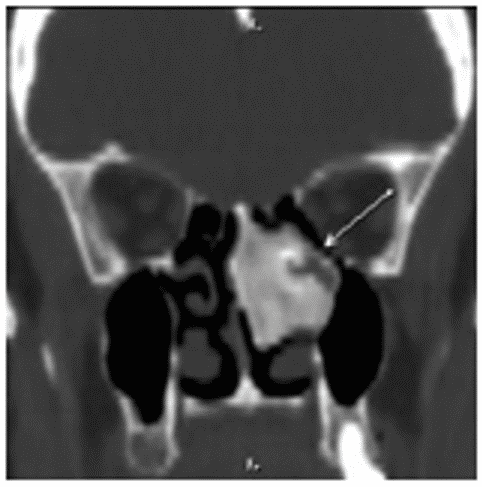

Хондрома на КТ представляется как объемное образование гетерогенной плотности с четко очерченными границами и очагами минерализации (рисунок 9).

Рис. 9. КТ носа и околоносовых пазух, коронарная (А) и аксиальная (Б) плоскости. Хондрома полости носа. Опухоль исходит из носовой перегородки, обтурирует правую половину носа, имеет четкие границы. Определяется смещение медиальной стенки правой верхнечелюстной пазухи, вторичные воспалительные изменения в верхнечелюстной и лобной пазухах справа